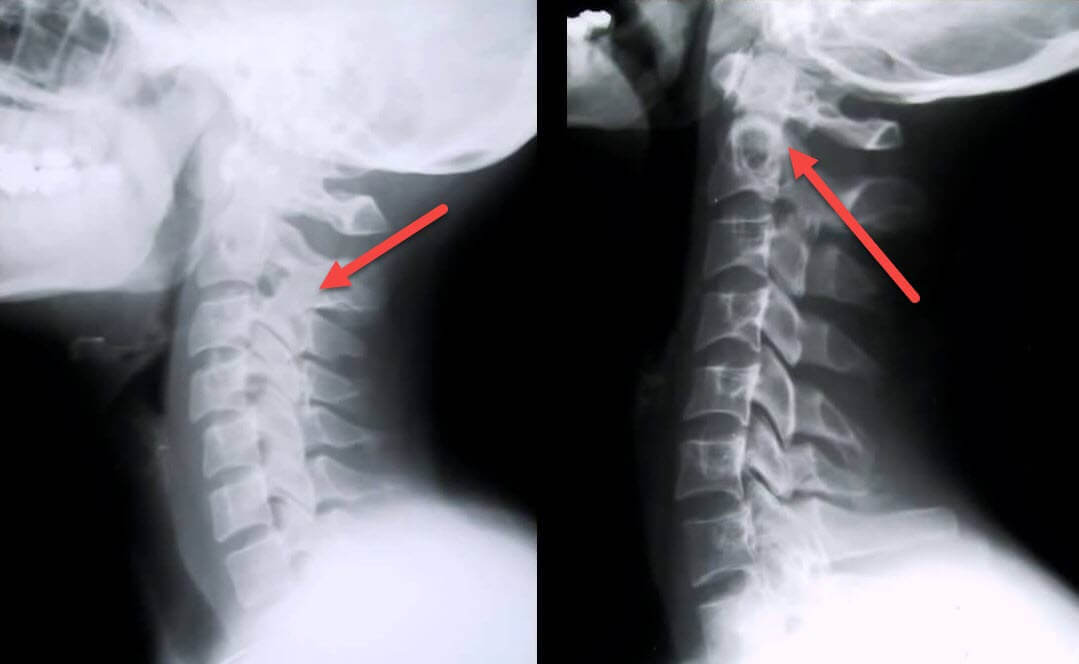

Самая информативная диагностическая процедура — рентгенография. Патологии 1 степени соответствуют 1 или 2 рентгенологическая стадия. На полученных изображениях визуализируются типичные признаки заболевания.

| Рентгенографические стадии шейного остеохондроза 1 степени | Характерные признаки |

| 1 стадия | Незначительные изменения изгиба позвоночника в шейном отделе, затронувшие один или несколько сегментов |

| 2 стадия | Небольшое утолщение межпозвонковых дисков, деформация крючковидных отростков, выпрямление лордоза, незначительные разрастания костных структур |